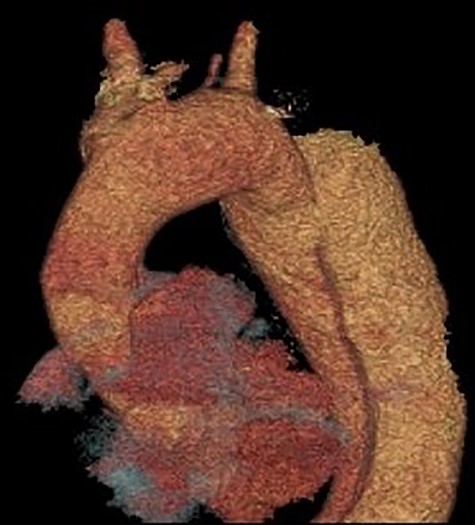

Coronal section CT scan images demonstrating the newly arranged epiaortic reconfiguration on left (A) and on the right (B) the deployed FET and antegrade flow in the descending thoracic aorta through the true lumen.

Cardiopulmonary bypass support was established using right atrial drainage and right axillary artery return. During cooling to 18°C, the aorta and epiaortic arch vessels were mobilized and encircled with tapes. At 21°C, the heart was fibrillated, aortic cross-clamp applied and antegrade cold blood intermittent cardioplegia administered to arrest the heart. At 18°C, neuroprotective protocol (topical ice to the head, intravenous steroids and mannitol administration with near infrared spectroscopy monitoring of cerebral saturations) was instituted and circulatory arrest commenced. The ascending aorta was transected 1 cm proximal to innominate artery and aortic arch inspected. Selective antegade cerebral perfusion was commenced. The aortic arch was divided in Zone 2 in order to protect the recurrent laryngeal nerve. The origin of the aberrant left vertebral artery and left subclavian artery were oversewn with a running 4/0 prolene suture. A 30/32/150 mm Thoraflex stent graft was deployed into the true lumen of the descending aorta. The cuff on the stent graft was anastomosed to the distal arch. Attention was then directed to the left common carotid and innominate arteries that were fashioned and anastomosed to the corresponding grafts on the stent graft. The aortic cross clamp was applied on the ascending aorta portion of the stent graft and total body circulation and rewarming was reinstituted. The ascending aorta was anastomosed to the stent graft 1 cm proximal to the innominate artery. A thorough de-airing drill was undertaken, the aortic cross clamp released and heart perfused. The graft on stent graft corresponding to the left subclavian artery was anastomosed and the origin on the aortic arch was oversewn. A 6-mm Dacron graft was then anastomosed to the transected left vertebral artery and origin on the aortic arch oversewn. The 6-mm Dacron graft was then anastomosed to the 8-mm side arm on stent graft corresponding to the perfusion arm. When fully rewarmed, cardiopulmonary bypass support was successfully weaned off and patient was in sinus rhythm requiring no inotropic support. Postoperatively, the patient made an uneventful recovery and was subsequently discharged home without complications and seen in the outpatient clinic as part of their routine surveillance. Computed tomography (CT) imaging performed as an outpatient demonstrated normal graft appearances, aortic arch and epiaortic vessel configurations (Fig. 3).

Our case demonstrates the successful use of FET for complicated TBAD as demonstrated previously [10]. The aberrant left vertebral artery originating directly from the aortic arch in the Zone 2 region is the most commonly observed variant, its incidence in a four-vessel epiaortic vessel configuration ranges from 0.68 to 5% [7]. Furthermore, an aberrant left vertebral artery is associated with a higher incidence of arterial dissection ranging from 0.9 to 1.9% [8]. Concerning aortic arch anomalies, the anatomical configuration of an aberrant left vertebral artery in the Zone 2 region pertains to challenging anatomy for TEVAR deployment. However, hybrid TEVAR with stent deployment into the conventional Zone 2 position and cervical transposition of the left vertebral artery to the left common carotid artery has been described [9]. Similarly, hybrid TEVAR with supra-aortic total debranching of the epiaortic vessels and cervical transposition of the left vertebral artery to the left common carotid artery with stent deployment into the Zone 2 position has also been reported [10]. Although not previously described, the surgical technique of reanastomosing the aberrant left vertebral artery to a Dacron graft and subsequent anastomosis to the perfusion limb of the Thoraflex graft mitigates the need for any concomitant cervical anastomosis of the aberrant left vertebral artery and favourably addresses this rare anatomical variation.